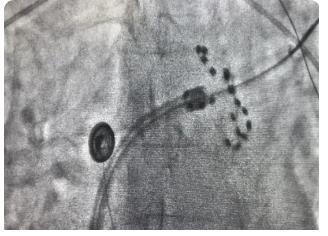

上图为X线下farapulse导管的两种形态:网篮状(左)和花瓣状(右)